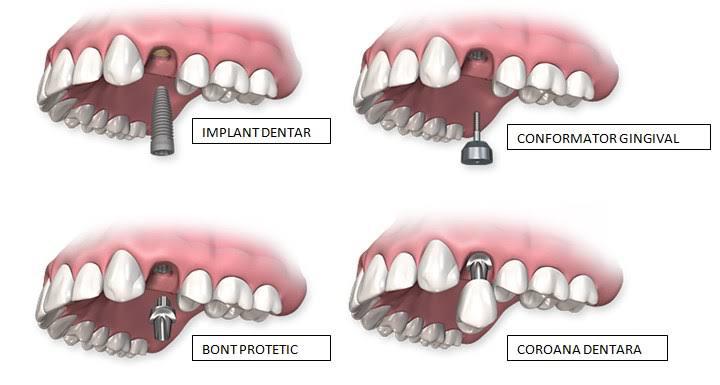

Etapele tratamentului cu implant denta

1. Consultația și planificarea

Evaluare clinică, investigații radiologice și stabilirea planului de tratament.

2. Inserarea implantului

Procedură chirurgicală realizată sub anestezie locală, în condiții de siguranță.

3. Perioada de vindecare (osteointegrare)

Implantul se integrează progresiv în os.

4. Reabilitarea protetică

Aplicarea lucrării definitive, adaptată funcțional și estetic.